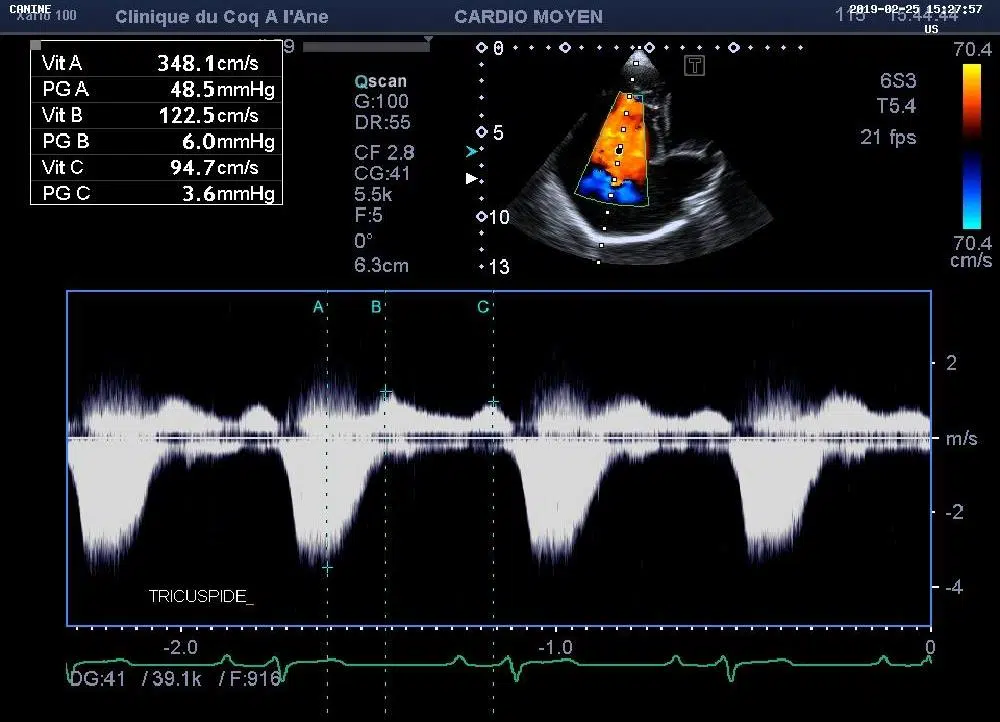

• 2 échographes dédiés aux petits animaux munis respectivement de 2 et 4 sondes